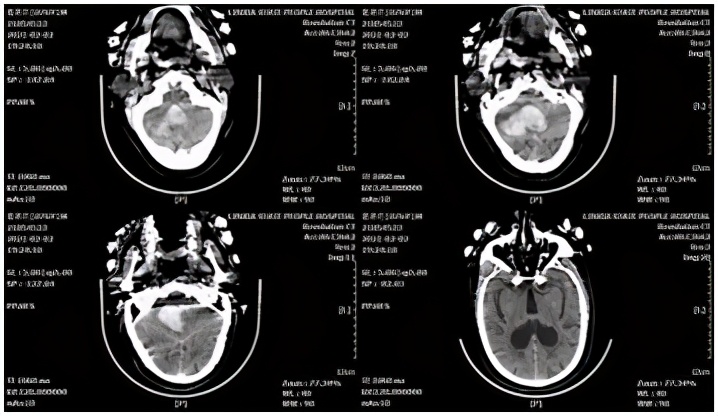

小脑出血病例,患者男性,77岁。主因"突发意识障碍,恶心、呕吐4小时",于2021-02-02,急诊以"高血压脑出血"收入院。头颅CT示:右侧小脑出血破入第四脑室,梗阻性脑积水形成。

术前头颅CT

术中采用 幕下 旁正中入路,并用血肿-脑脊液置换技术,最终清除小脑半球、第四脑室全部血肿,术后血肿腔不放置引流管,取得了良好效果。

术后头颅CT